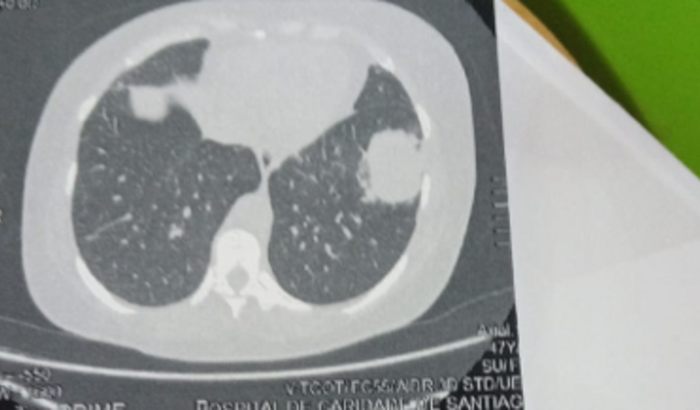

Eu Brenda Batista de Oliveira ,criei essa vaquinha para ajudar minha tia Ana Inês Batista de Oliveira , que está passando por uns problemas de saúde, ela está com um tumor no pulmão esquerdo e é grave , precisamos da ajuda de vocês , pois são muitos exames caros e gastos com medicação , e também os custos das viagens que é necessário ela fazer , no momento a situação financeira não é boa , por isso peço encarecidamente a ajuda de vocês ! Que Deus abençoe a vida de todos 🙏 obrigada pela atenção!